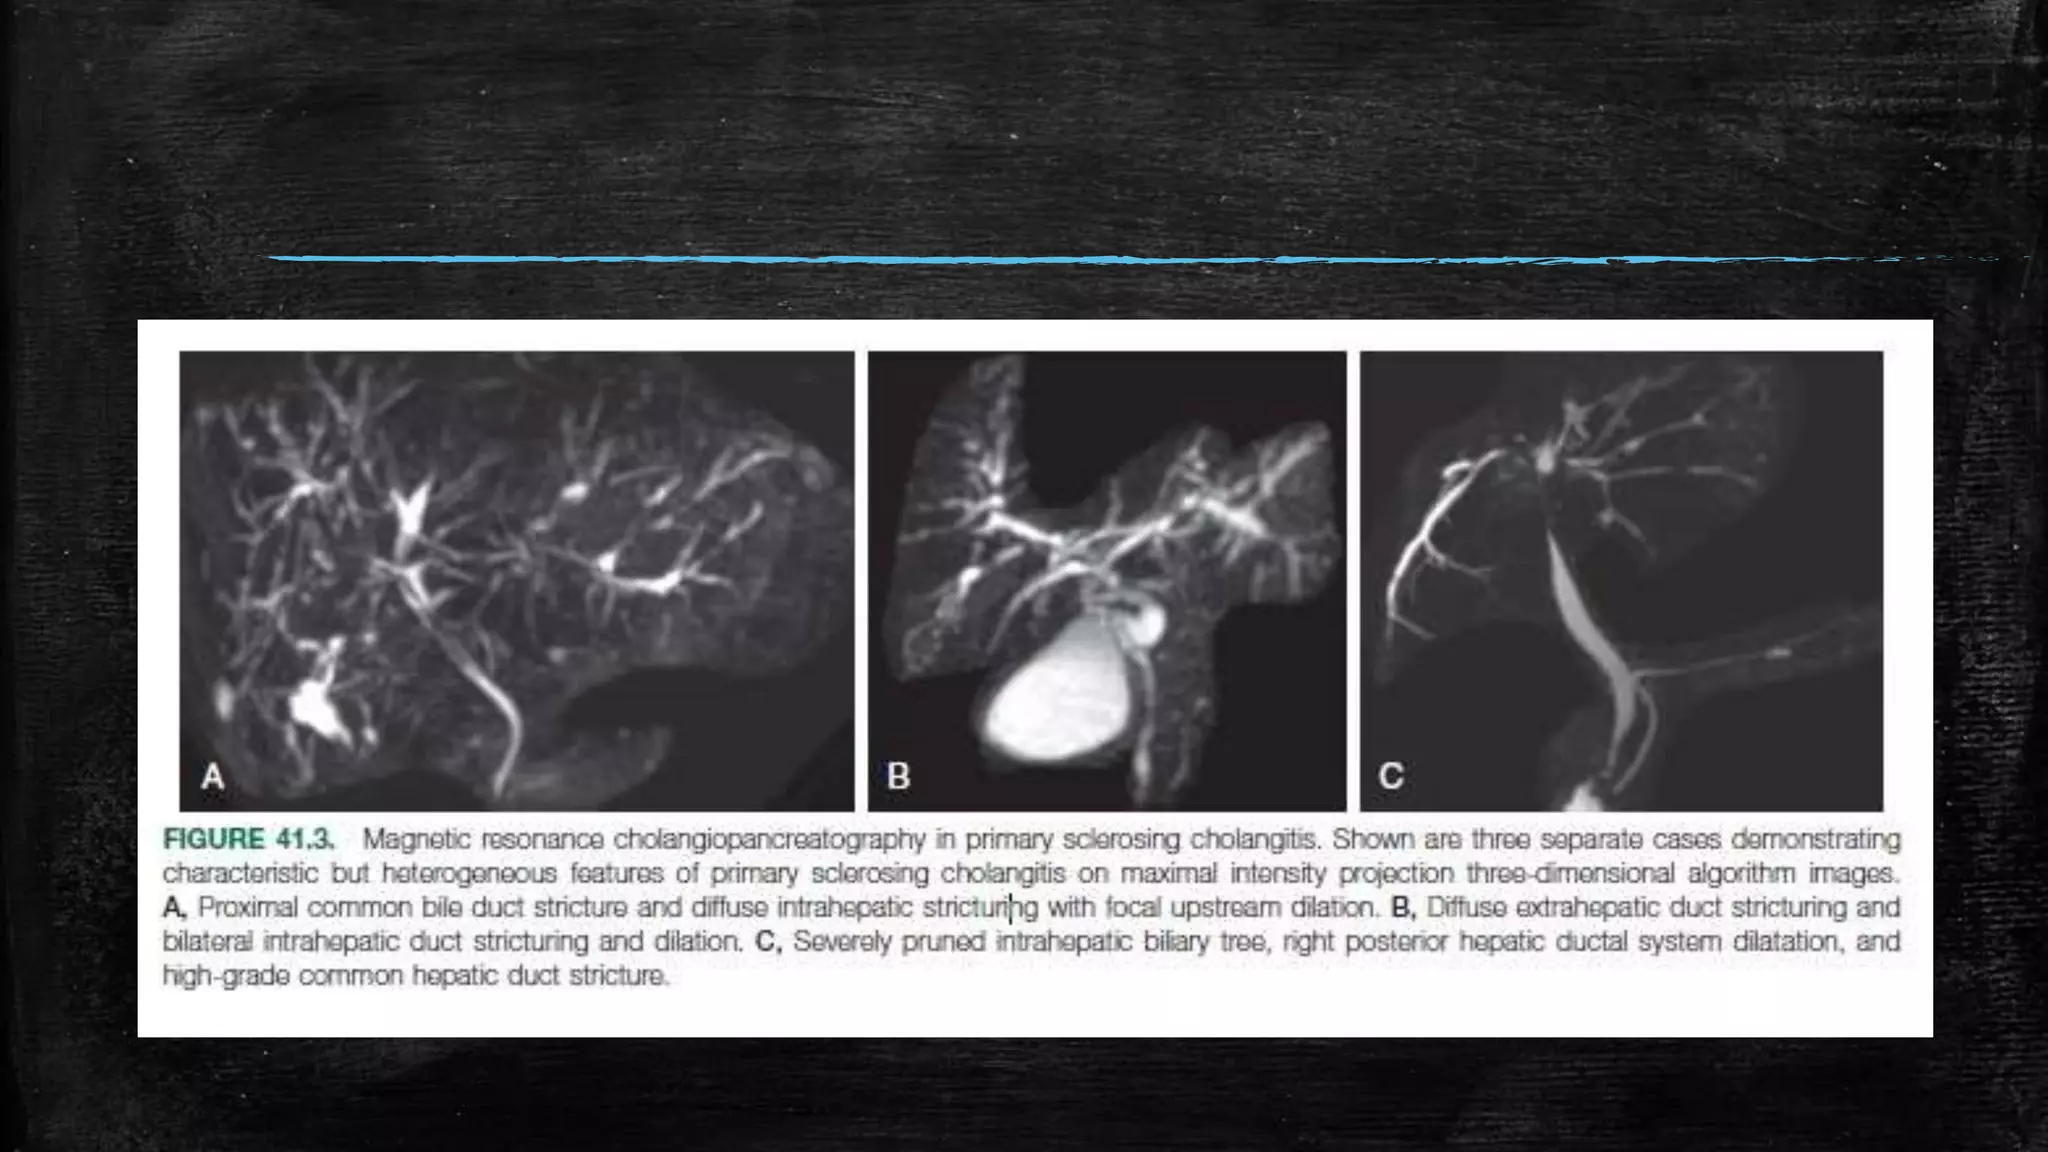

▪ (2) cholangiography demonstrating multifocal intrahepatic and/or

extrahepatic biliary strictures and segmental dilations

Diagnosis ▪ Clinical featureswith ▪ (1) a chronically cholestatic serum biochemical profile ▪ (2) cholangiography demonstrating multifocal intrahepatic and/or extrahepatic biliary strictures and segmental dilations ▪ (3) compatible features (e.g., chronic cholangitis, ductular proliferation, and periductal fibrosis) on liver biopsy